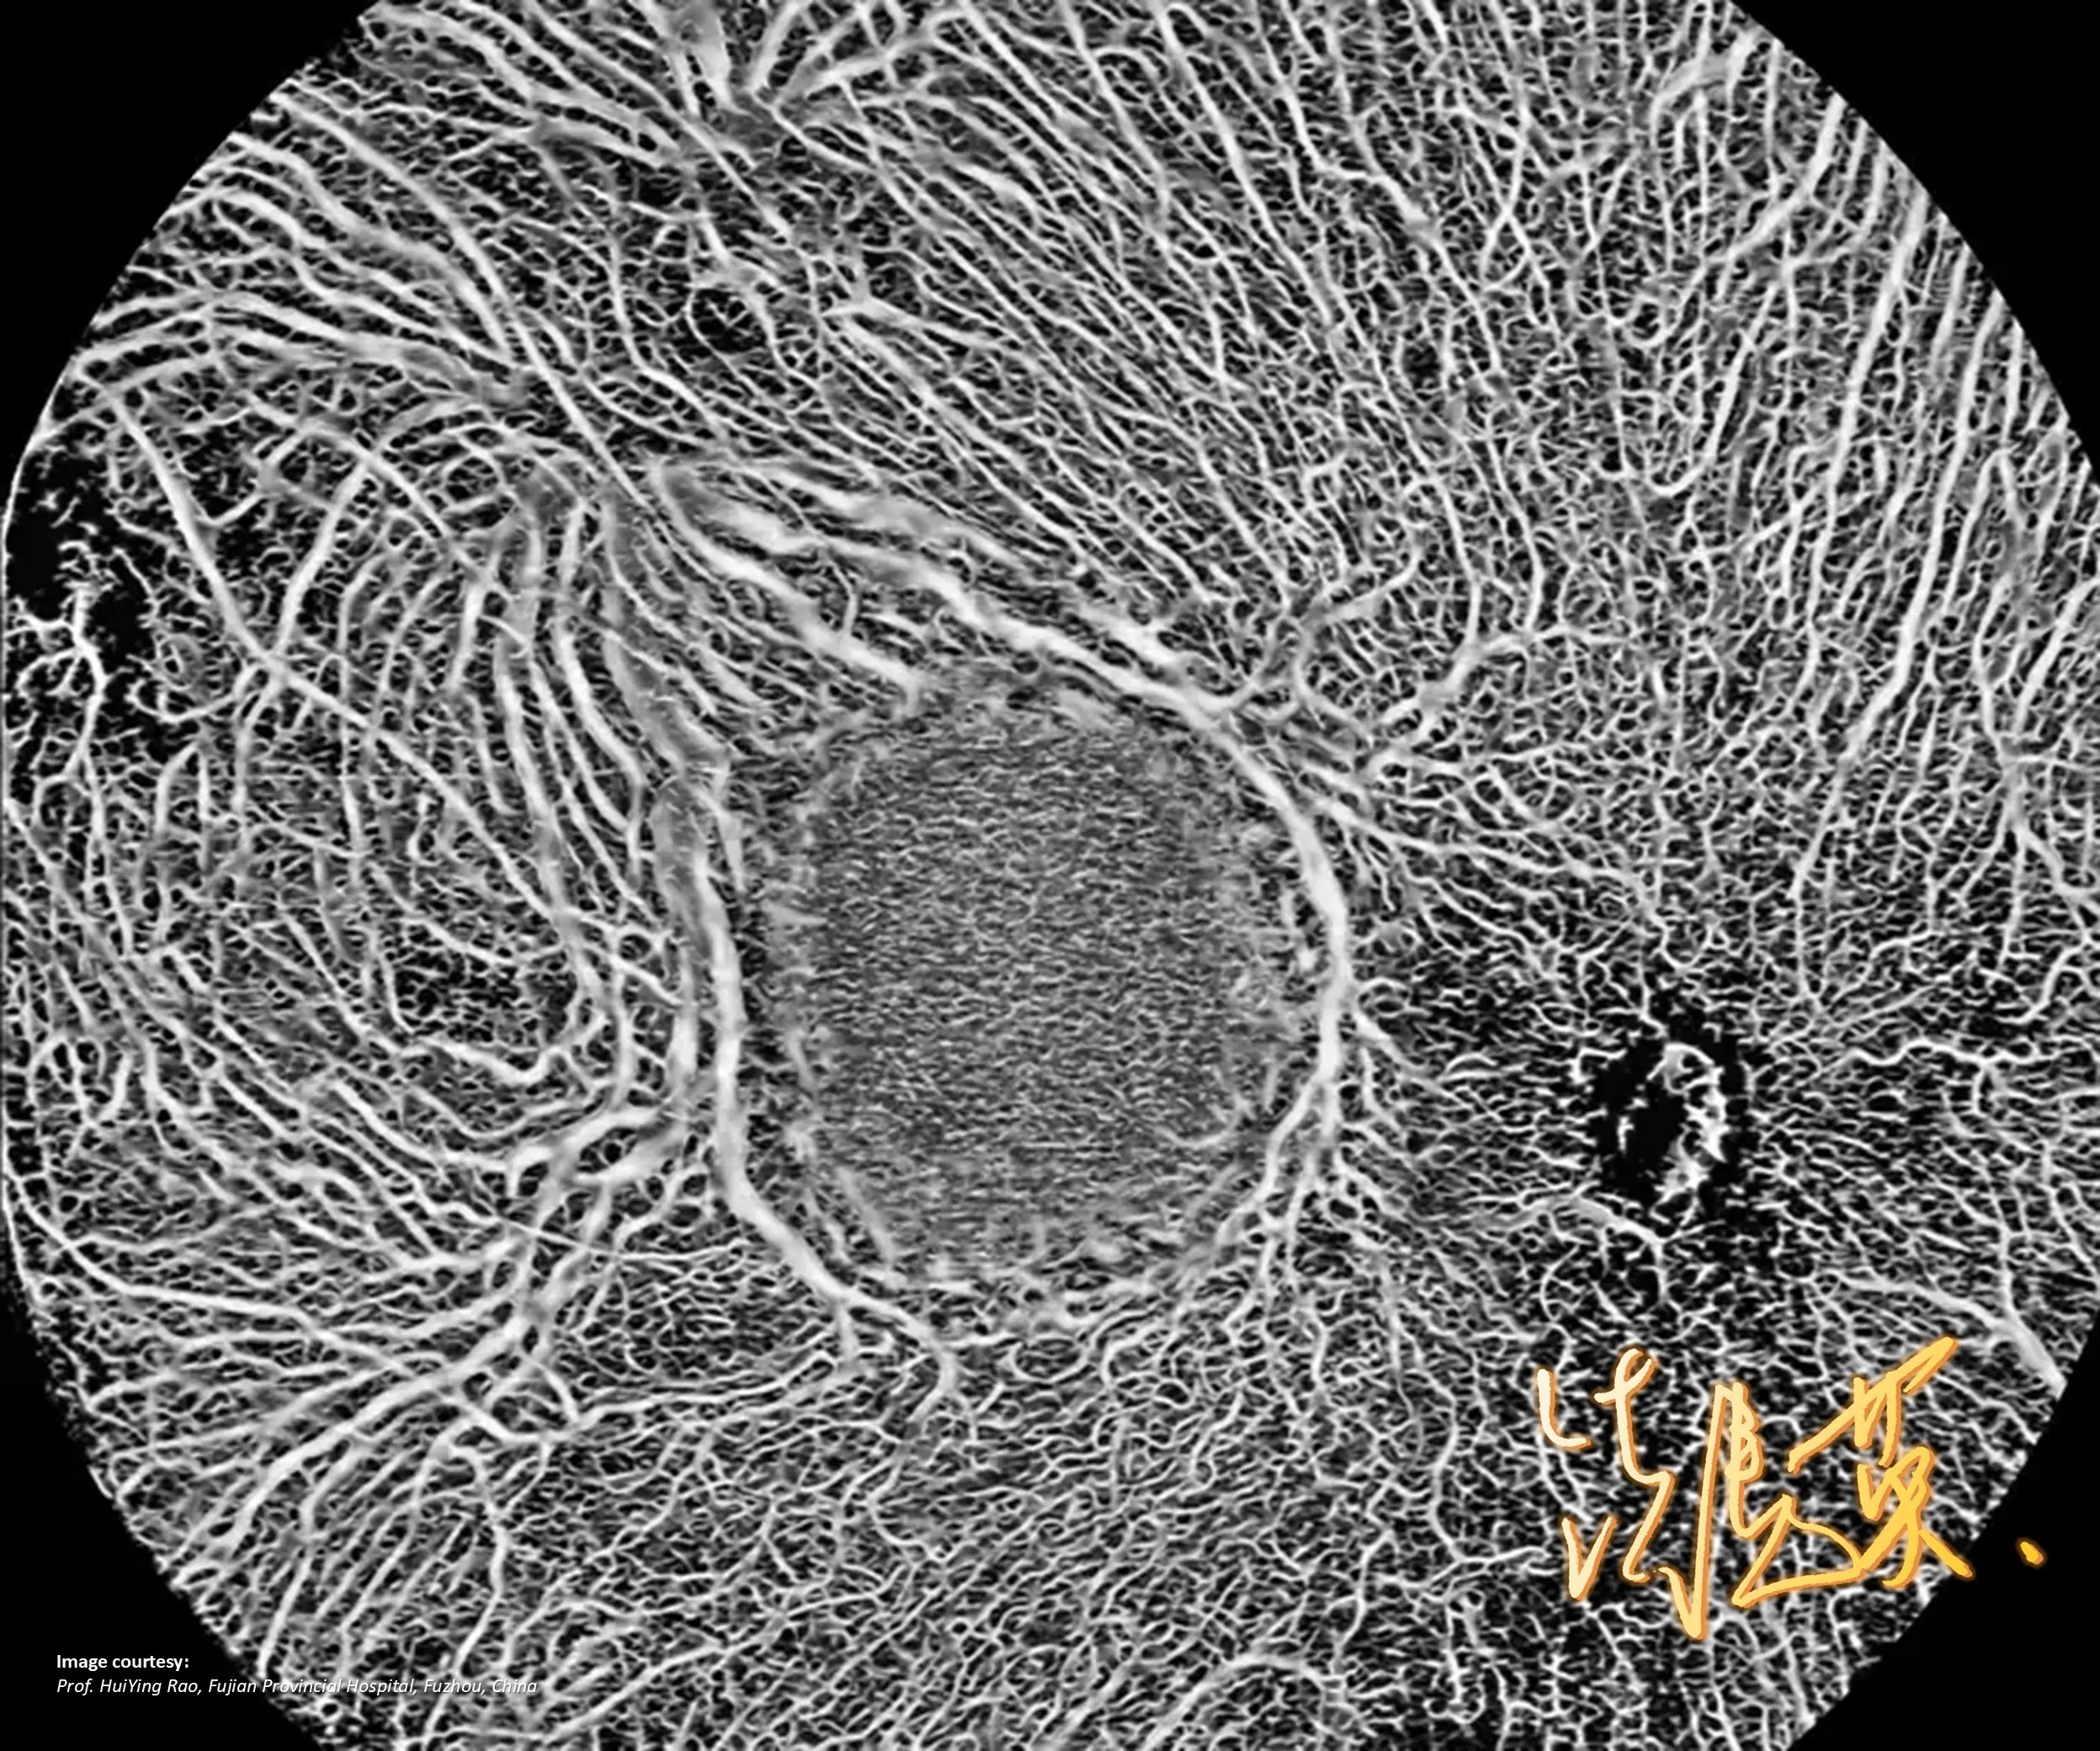

Full-range SS-OCT YAlkaid skanuje jednocześnie przedni i tylny segment oka w jednym badaniu, a BMizar umożliwia ultra-szerokokątne pole 24×20 mm, co pozwala wykryć zmiany obwodowe.

Oba urządzenia obsługują zarówno OCT, jak i OCTA, oferując algorytmy AI do automatycznej segmentacji warstw, analizę ilościową naczyń oraz 3D-rekonstrukcję. To kompleksowe narzędzia diagnostyczne.

GALERIA PRZYPADKÓW

Kliniczne znaczenie

innowacji